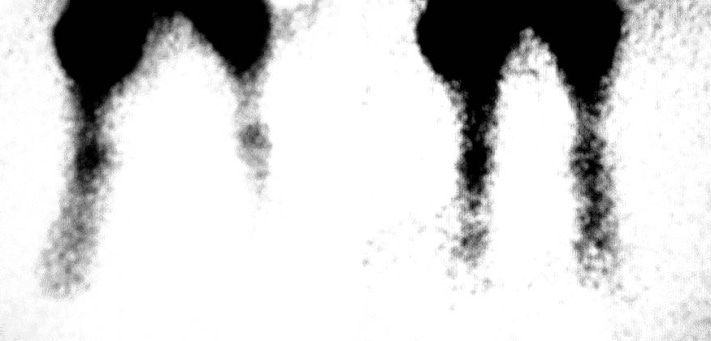

На фото: слева обмороженная лапка кролика до воздействия аппарат, справа - после.